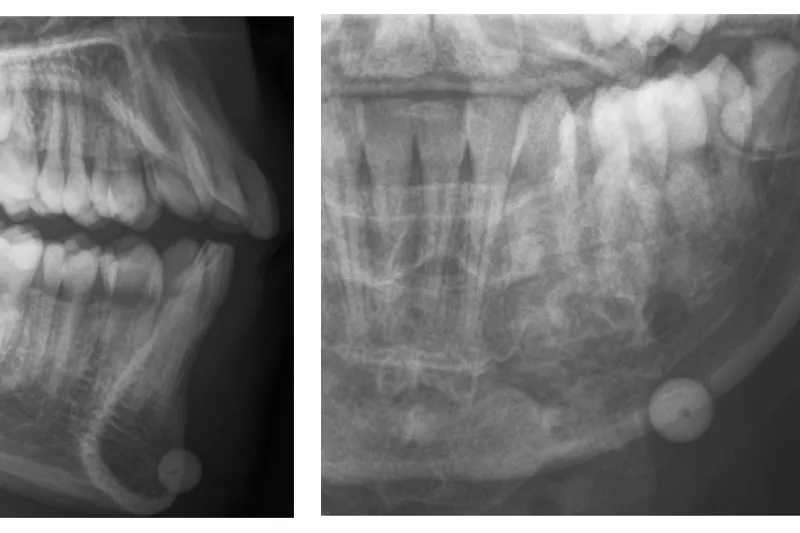

Case study – A 12-year-old boy was admitted to the Department of Oral and Maxillofacial Surgery, Aalborg University Hospital, for removal of a softgun plastic bullet in the lower lip. The injury had happened 10 days prior during play without use of safety equipment. An x-ray showed a well-defined round radiopaque foreign body located in the soft tissue near the mandibular base in region 33, 34. The bullet was removed through an intraoral approach with an non-complicated healing.